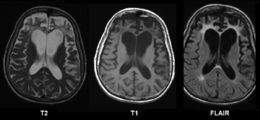

皮克氏症的大脑磁共振成像 |

皮克氏病(Pick's disease,PiD),为一种渐进性痴呆。通常开始于中年,形成于早年,其反应为缓慢渐进的性格改变与社交能力衰退,并伴有智力、记忆和语言组织能力损伤,此外还会有情感淡漠、亢奋和偶然的椎体外系症状。